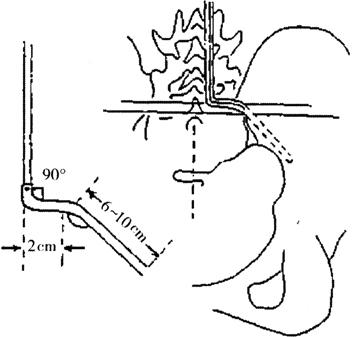

(3)髂骨钻孔:在骶棘肌下面,S1~S2棘突间中点相对应的髂骨后嵴上近骶髂关节处打孔。先取一根骨圆针沿坐骨切迹上方1.5cm处插入髂骨内外板之间,钻入6~10cm,注意勿误入骶髂关节间隙,不要穿透髋臼顶。

(4)弯棒:测量几个距离,即钻入口至S1棘突距离(骶段),一般为1.5~2.0cm,插入髂骨内长度(髂段),一般7cm左右(6~10cm,不能少于6cm),L3至S1距离(腰段)。然后取两根长60cm,直径5~6mm的Luque棒,按上述测得的距离弯棒,而且髂段与骶段夹角是45°~65°(在近矢状面上),腰段与骶段夹角为90°(在额状面上),再将腰段棒在矢状面上预弯出与腰前凸相一致的弧度。